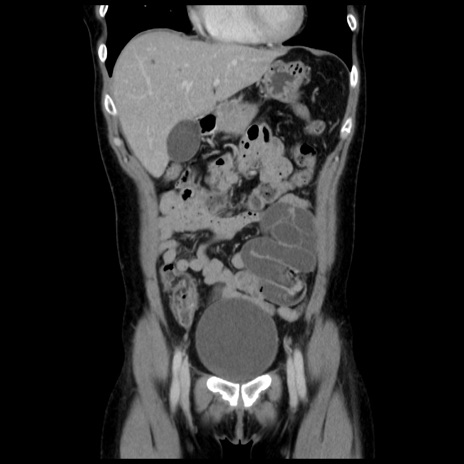

症例10(冠状断像)

【症例】 50歳代女性

【主訴】 腹痛

【現病歴】前日生レバーを食べた。今朝に排便あり。 昼前に突然発症の腹痛を生じ、当院救急外来を受診した。

【既往歴】 子宮筋腫にてで子宮全摘後

【身体所見】 意識清明、腹部:平坦、軟、下腹部やや左を中心に圧痛・反跳痛あり、筋性防御あり

【データ】WBC 7800、CRP 0.07